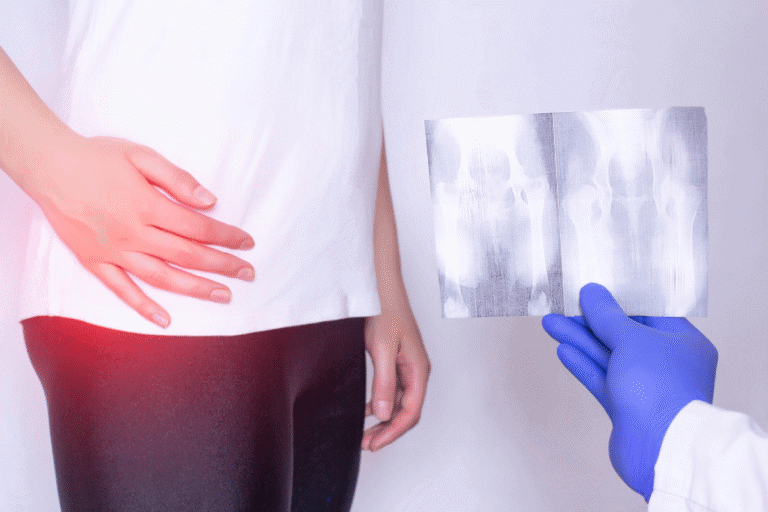

Desde el envejecimiento, diabetes, cáncer, hiperlordosis, colesterol, autofagia y un largo etc. Todo ello ligado al ejercicio y a los efectos que tiene éste sobre el cuerpo.